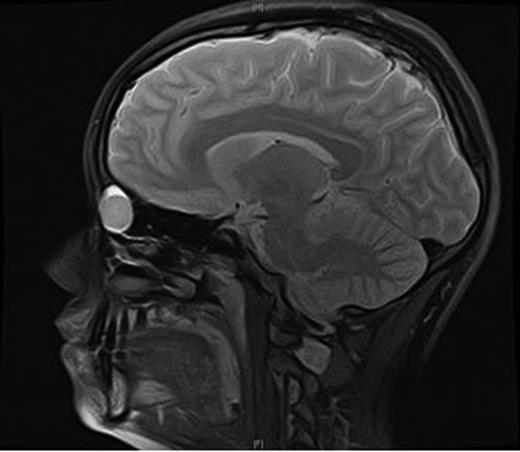

An MRI scan of the orbits showed a well-defined, thin-walled 22 × 16 mm cyst medial to the left orbit containing fatty/proteinaceous material, which was lying within and mildly expanding the left ethmoid air cells (Figs 1–3).

A CT scan of the paranasal sinuses and orbits revealed the cystic expansile 1.6 cm mass at the left medial canthus to be of soft tissue density. The lateral wall of the mass expanded outwards into the orbit (suggesting an anterior ethmoidal mucocele) rather than being pushed medially (which could have been indicative of a dacryocystocele) (Fig. 4).